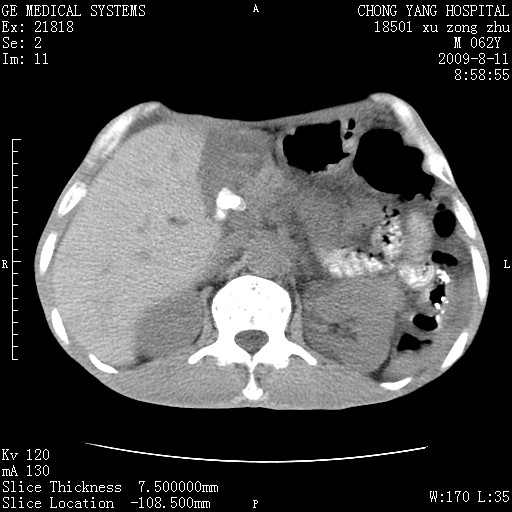

以下是引用杀毒软件在2009-8-11 16:35:00的发言:[br]肝内胆管扩张局限于左叶,胆管内有结石伴肝外胆管结石,胆管壁增厚呈弥漫性并发腹腔积液,胰腺边界模糊。[br][br]考虑---胆总管及肝内胆管结石继发胆管炎及胰腺炎,左肾下极囊肿,腹水。

以下是引用zjzjr在2009-8-11 17:35:00的发言:[br]肝内胆管扩张局限于左叶,胆管内有结石伴肝外胆管结石,胆管壁增厚呈弥漫性并发腹腔积液。[br][br]考虑---胆总管及肝内胆管结石继发胆管炎,左肾下极囊肿,腹水。